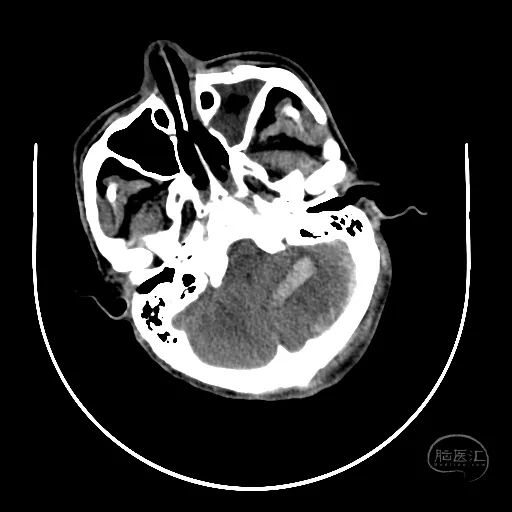

2小时后复查颅脑CT显示第四脑室受压消失。

小脑挫伤灶水肿较前加重,脑干及小脑半球低密度改变。

硬膜外血肿无明显变化。

右额叶脑挫裂伤并脑内血肿形成,中线结构明显移位。

左侧脑室有扩张表现。